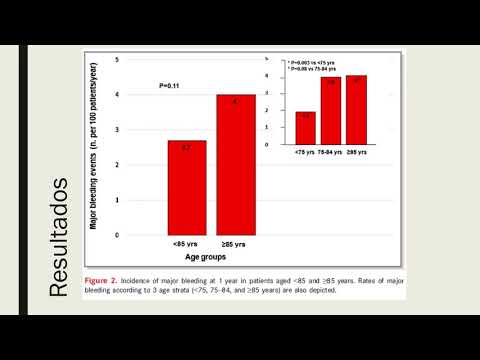

Riesgo tromboembólico, sangrado y efectos de diferentes antitrombóticos en la FA de ancianos. Dra. Ana Laura Mori. Residencia de Cardiología. Hospital C. Argerich. Buenos Aires